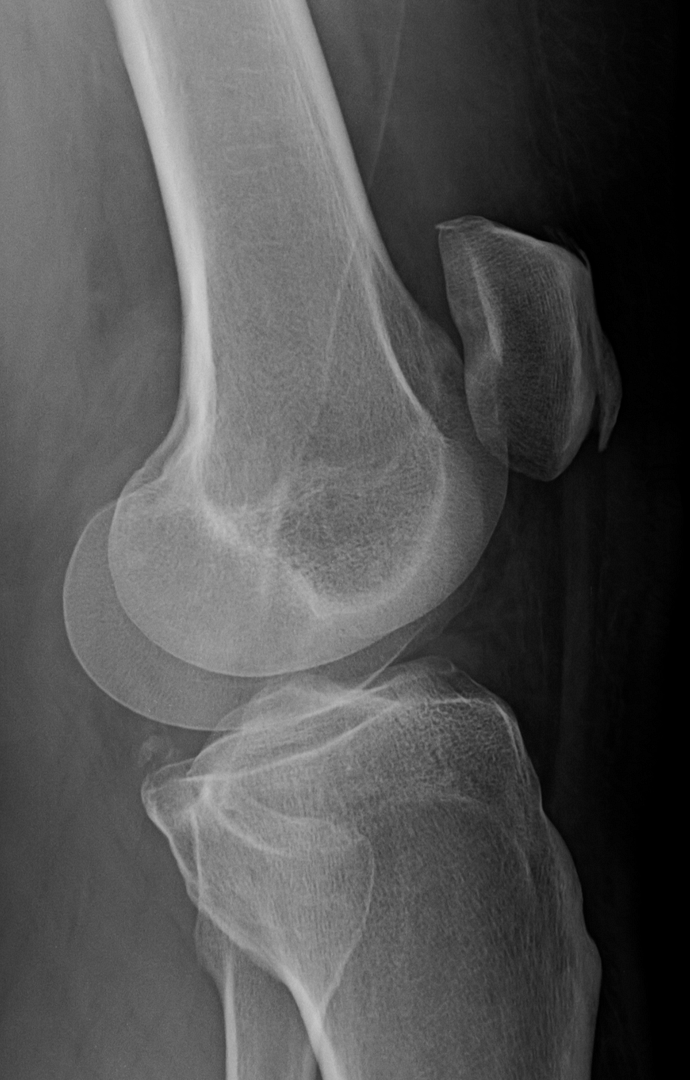

Your sunrise pateler views (bottom knee cap floating in space view) are worrying. You are developing bone avulsions (the part where it looks like it is separating) most likely due to impact injury coupled with straining tendons. You got to start wearing knee pads for what ever you are doing that is impacting them. If that continues in the same path, even walking will be a chore.

On the lateral view I can see see a section of calcification on the anterior aspect. ................... The worrying part is just bellow the calcium I see a region that looks like a chip fracture or an older one. Its the diagonal line with the offset. Of course, I could just be nitpicking and just seeing something that is an optical illusion.